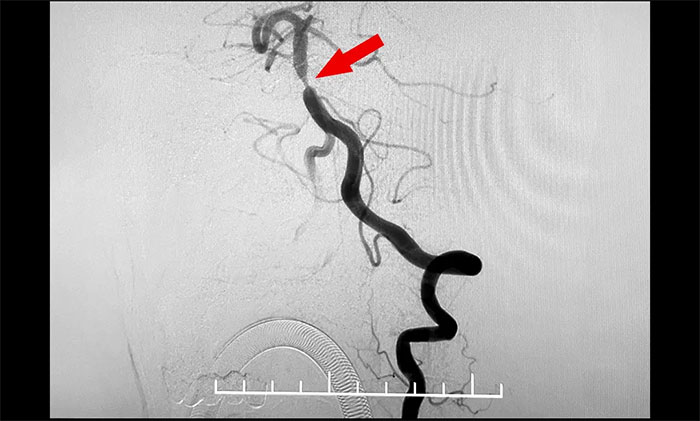

頭顱MRI+SWI+DTI提示腦干梗塞,雙側(cè)橋臂變性;雙側(cè)放射冠區(qū)、額頂葉散在腔梗、缺血灶;讋(dòng)脈HRMR平掃+增強(qiáng)提示基底動(dòng)脈管壁增厚伴重度狹窄。頭顱CTP顯示,右側(cè)頂枕顳葉局部腦組織灌注較對(duì)側(cè)稍減低。DSA提示基底動(dòng)脈中段重度狹窄。

4A腦血管病一科主任席剛明教授,4A腦血管病一科副主任王貴平博士會(huì)診指出,該患者為基底動(dòng)脈主干病變,呈現(xiàn)為“一線天”樣狹窄,考慮基底動(dòng)脈重度狹窄為患者右側(cè)肢體麻木并加重的根源。并且,狹窄處隨時(shí)可能形成血栓引發(fā)血管急性閉塞,一旦閉塞,患者將可能出現(xiàn)深昏迷、四肢癱瘓,甚至危及生命,可以說“命懸一線”,即使僥幸保住性命,大概率也會(huì)成為植物狀態(tài)或遺留其他嚴(yán)重殘障。

▲ 基底動(dòng)脈重度狹窄